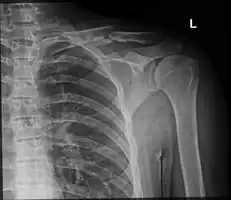

Clavicle fracture